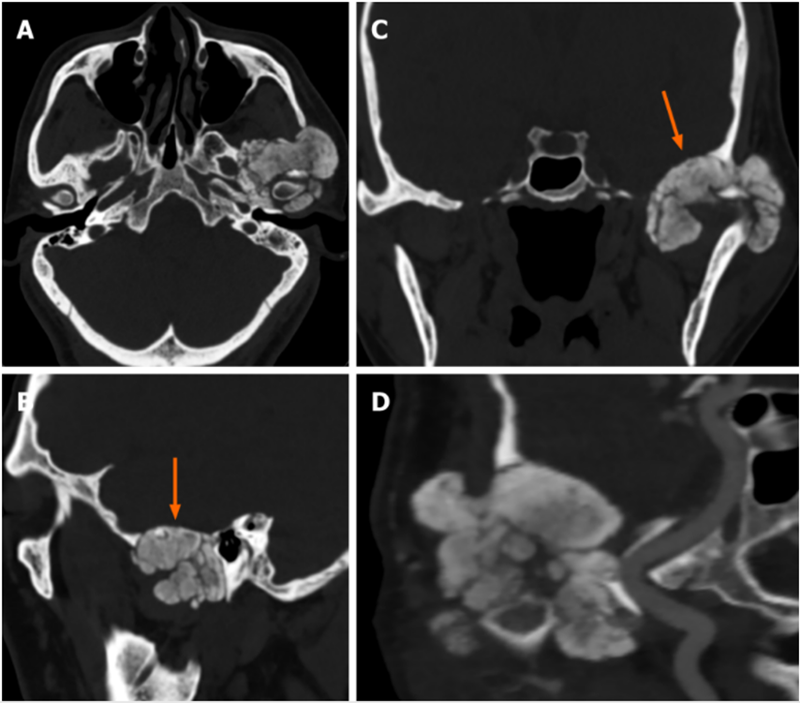

CPDD累及颞下颌关节

颞下颌关节侵犯了颅窝的钙焦磷酸沉积疾病